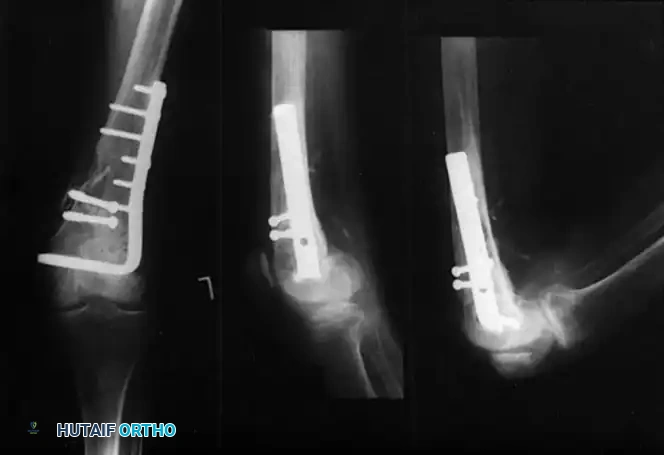

Plate and Screw Fixation: The AO Blade Plate

The AO supracondylar blade plate was one of the first devices to provide rigid enough fixation to allow early knee motion. While biomechanically robust, its insertion is technically unforgiving. The blade requires simultaneous accurate insertion in three planes (varus/valgus, flexion/extension, and internal/external rotation).

Schatzker and Lambert highlighted the technical difficulty of this implant, noting that good results were obtained in 71% of fractures with stable fixation, but plummeted to 21% if fixation was inadequate. Siliski, Mahring, and Hofer later reported 81% good or excellent results in severe Type C fractures using blade plates, though intentional shortening of 1 to 3 cm was often required in older patients to achieve bony apposition and stability.

Image

Biomechanical principles of blade plate insertion, requiring precise triplanar alignment.

Provisional K-wire fixation establishing the trajectory for the seating chisel.

Seating chisel insertion preparing the channel for the blade plate.

Final seating of the blade plate and application of interfragmentary compression.